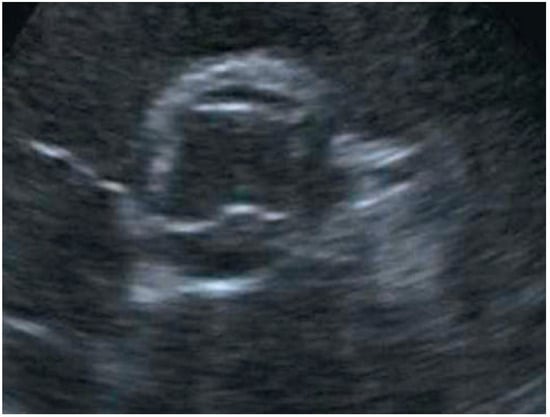

Die transthorakale Echokardiographie zeigte (trotz schlechter Schallbarkeit) eine Aortenklappe mit vier Kommissuren und viereckiger Öffnungsfläche, so dass der Verdacht auf eine quadrikuspide Aortenklappe (QAK) bestand (Figure 1).

Figure 1. Transthorakales Echokardiogramm mit Kurzachsenschnitt: Trotz schlechter Bildqualität ist zu erkennen, dass es vier Kommissuren gibt. Die Öffnungsfläche ist quadratisch.